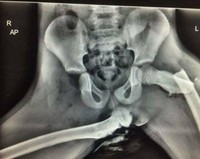

Jakarta - Akun Instagram Medicalpedia menampilkan foto medis sejumlah pasien. Melihatnya menimbulkan reaksi, mulai dari tecengang, melotot, ngeri hingga merinding.

Bukan Editan Photoshop, Deretan Foto Medis Bikin Melotot dan Merinding